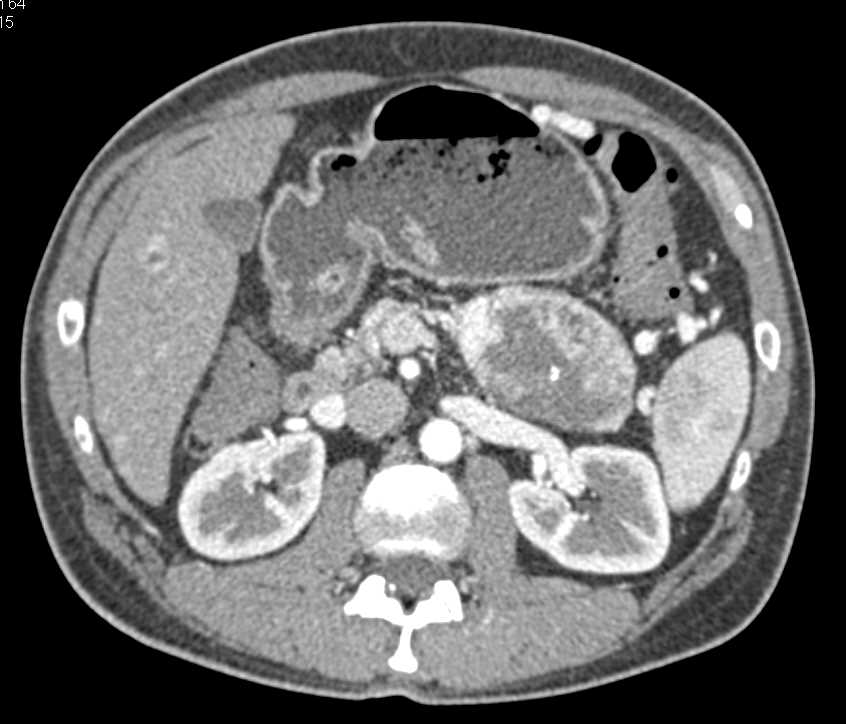

Neuroendocrine Tumor in the Tail of the Pancreas